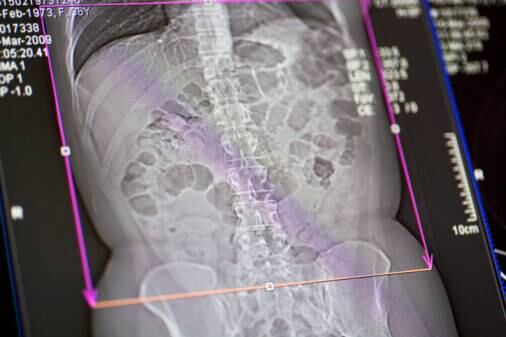

Tras efectuarle una tomografía computarizada a la adolescente, se encontró «una masa bien definida», indicándose que esta presentaba elementos de tejido adiposo y secciones de formaciones semejantes a huesos.

Luego de los análisis de rigor se determinó que tenía fetus in fetu, realizándose posteriormente una operación para extraerle el «gemelo».

Allí, se halló un cuerpo que medía 30×16×10 centímetros. Este tenía además pelos y «múltiples dientes».